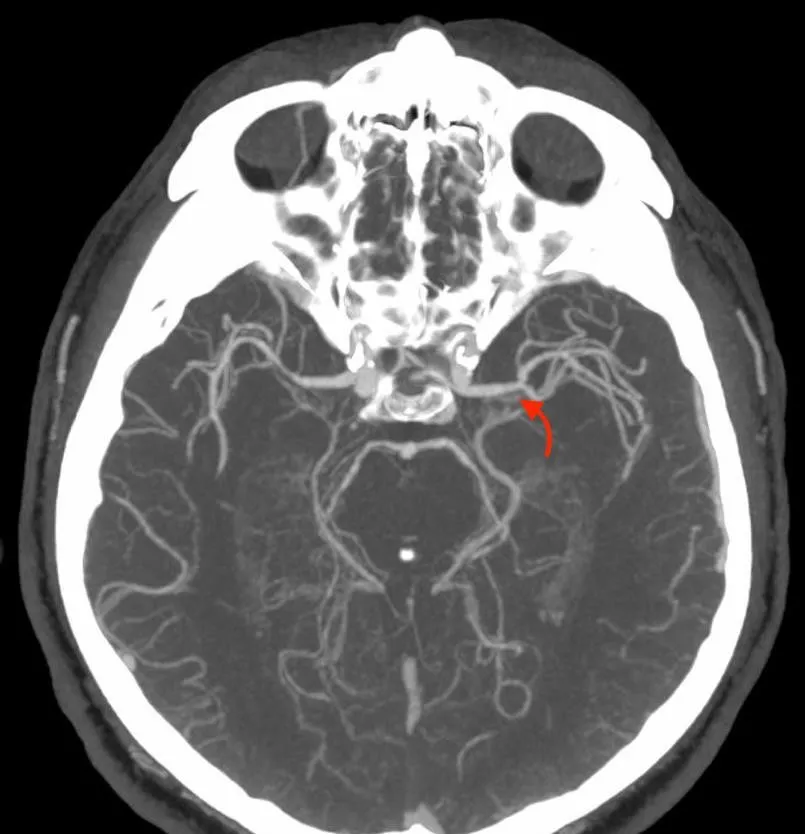

Рисунок 2. Результати МСКТ-ангіографії церебральних судин.

Результати МСКТ-ангіографії (ліворуч коронарна, праворуч – аксіальна MIP-реконструкція) свідчили про оклюзію лівої внутрішньої сонної артерії (ВСА) в екстракраніальному сегменті

(жовта стрілка) та оклюзію лівої середньої мозкової артерії (СМА) в сегменті М1 (червоні стрілки).

Відповідно до результатів нейровізуалізації та візуалізації церебральних артерій у пацієнта Д. був діагностований ішемічний інсульт, що обумовлений оклюзією великої мозкової артерії (лівої внутрішньої сонної артерії [ВСА] та лівої середньої мозкової артерії [СМА]). Згідно з результатами автоматичного обчислення, на момент дослідження об’єм ядра інфаркту у пацієнта Д. склав 24,6 см3, а об’єм зони пенумбри – 47,9 см3. Отже, об’єм зони пенумбри становив 194,7% об’єму ядра (співвідношення пенумбри та інфаркта майже 2:1). Зважаючи на це, ситуація була обговорена з лікарем-нейрохірургом С. В. Конотопчиком і о 14:45 пацієнт бригадою НМД «Оберіг» був доправлений у ДУ «НПЦ Ендоваскулярної нейрорентгенохірургії НАМН України» та спрямований одразу до операційної.